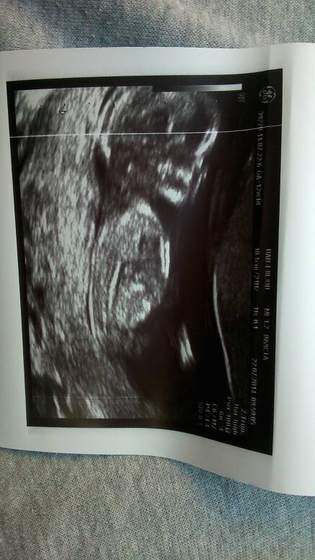

U mnie wszystko ok :-) płci nie chciał broj ujawnić :-P całe badanie z 30 min trwało wiec się naogladalam malucha ruchliwy a jak chwile polezalam na boku to ssal kciuka :-D

Jedynie coś z sercem lekarzowi nie pasowało ze.mocno biło czy coś dał skierowanie.na echo w 20tc ale z Niną to samo miałam ogólnie mówił żeby się nie martwić ze wszystko ok ;-)